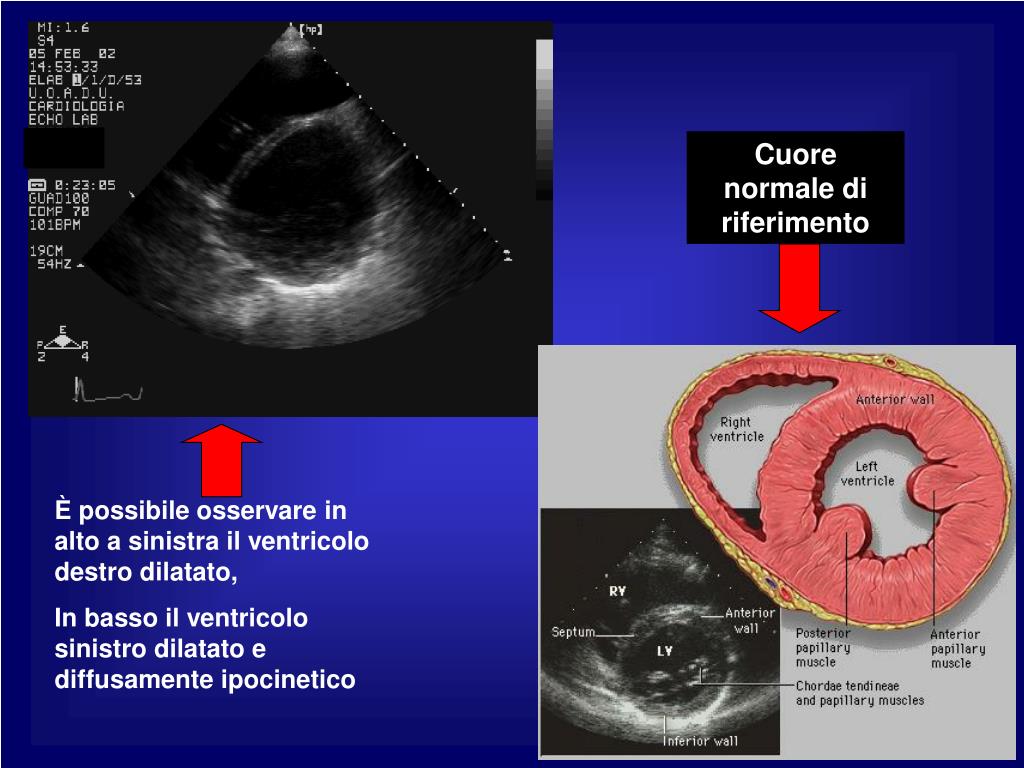

47. Cuore normale di riferimento È possibile osservare in alto a sinistra il ventricolo destro dilatato, In basso il ventricolo sinistro dilatato e diffusamente ipocinetico